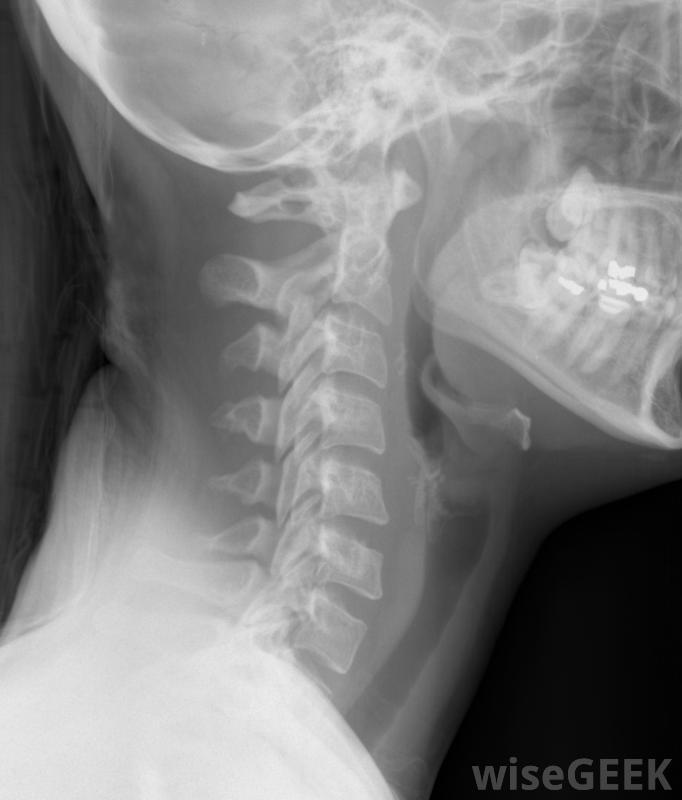

颈部的X光片,包括颈椎颈椎管狭窄症的常见原因仅仅是椎骨的磨损。随着年龄的增长,椎骨间的填充物,即椎间盘,变得越来越不灵活,椎骨开始压缩椎间盘。有些人的椎骨内侧出现骨刺,这些骨刺伸入椎管,导致椎管狭窄,如果足够狭窄,就会对脊髓造成损伤,脊髓损伤被称为脊髓病,它会引起一些非常明显的症状